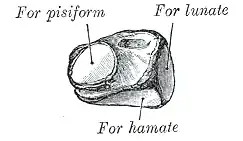

The left triquetal bone | |

The triquetral bone may be distinguished by its pyramidal shape, and by an oval isolated facet for articulation with the pisiform bone. It is situated at the upper and ulnar side of the carpus. To facilitate its palpation in an exam, the hand must be radially deviated so that the triquetrium moves out from under the ulnar styloid process. The triquetrum may be difficult to find, since it also lies under the pisiform.

The superior surface presents a medial, rough, non-articular portion, and a lateral convex articular portion which articulates with the triangular articular disk of the wrist.

The inferior surface, directed lateralward, is concave, sinuously curved, and smooth for articulation with the hamate. The dorsal surface is rough for the attachment of ligaments.

The volar surface presents, on its medial part, an oval facet, for articulation with the pisiform; its lateral part is rough for ligamentous attachment.

The lateral surface, the base of the pyramid, is marked by a flat, quadrilateral facet, for articulation with the lunate.

The medial surface, the summit of the pyramid, is pointed and roughened, for the attachment of the ulnar collateral ligament of the wrist.